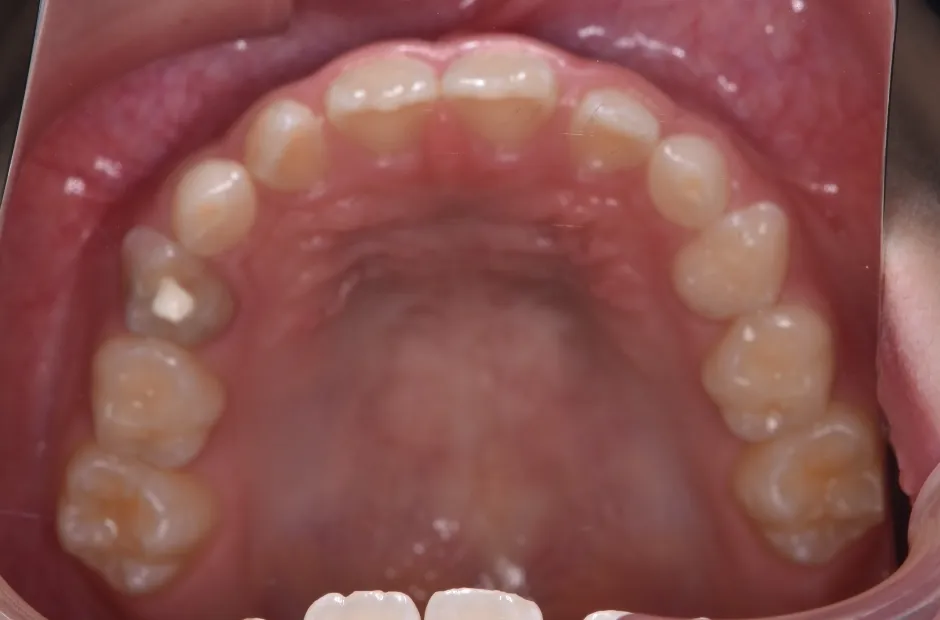

拡大床装置

叢生

| 診断名・主訴 | 叢生 |

|---|---|

| 年齢・性別 | 10歳・女性 |

| 治療期間・回数 | 2年半 |

| 治療に用いた主な装置 | 拡大床装置 |

| 抜歯部位 | なし |

| 治療費 | 30万円(税抜) |

| リスク・副作用 | 装置による違和感・疼痛・歯肉退縮・歯根吸収・虫歯のリスクなど |

治療前

治療中

治療後